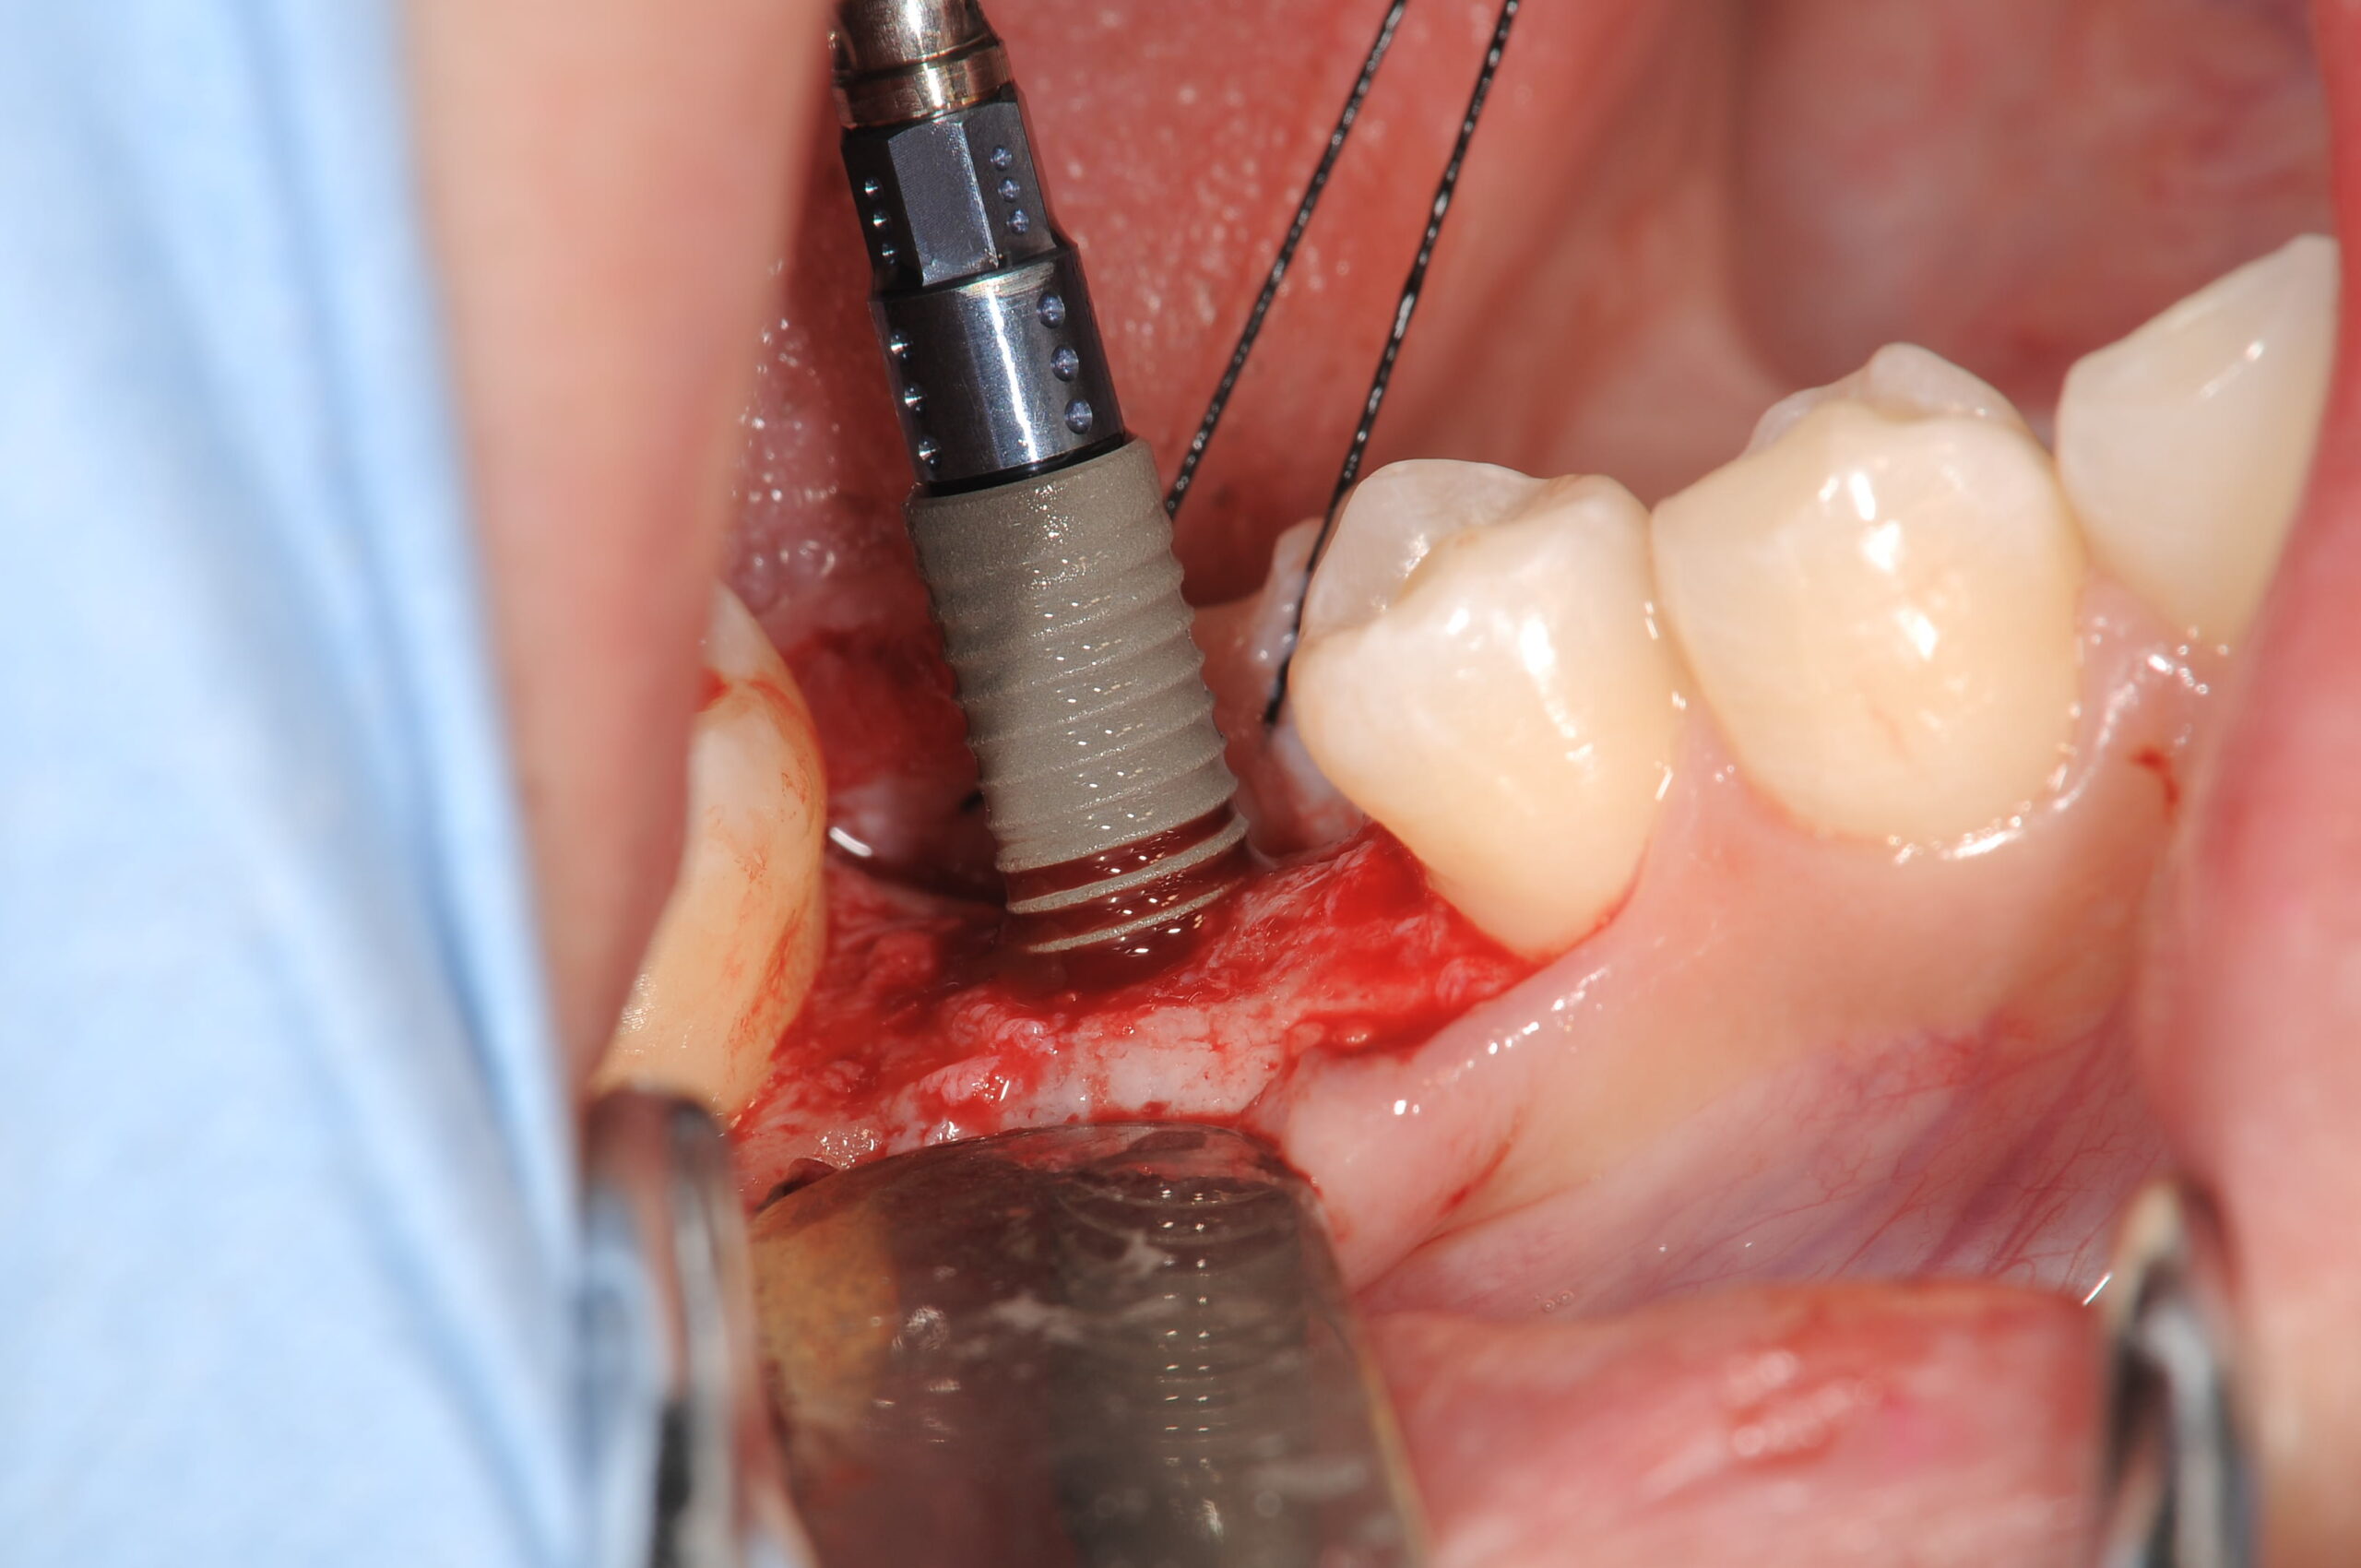

3か所にストローマンのボーンレベルインプラントSLActiveを埋入しました。

使用したストローマンボーンレベルインプラントSLActiveです。

右下に埋入しているところです。親水性の表面を持っているために、血液が上がってきます。